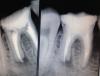

Каплан Опубликовано 19 марта, 2013 Поделиться Опубликовано 19 марта, 2013 (изменено) 26. асимтоматичен. ранее попытка ретрита, пройден мезиальный. (по снимку 1). и немного небный. зная что резорцинка, думаю сниму пломбу, гляну что и как, если что просто переставлю и все.открыл. локализовал устья. нашел пропущенный мезиальный. распаковал гутту в мезиальном и небном. бился бился в небный, не идет. дистальный до упора. мезиальный (запакованный) до апекса, найденный до упора. кальций.пришла в след.визит. я опять с мыслью отмою и запакую.в итоге прошел небный (канал был чуть дистальнее, мезиальнее ступенище). дистальный до упора. под занавес запикал потеряшка-мезиальный... и вот в самый последний момент, смотрю, а в мезиальном еще кусок гутты, который мне не нравится. я его спредером ковырнул, а там прям канал. обработка до упора.итого 3 мезиальный, дистальный и небный. кальций.сегодня запаковал.http://img855.imageshack.us/img855/2899/68794825.jpg Uploaded with ImageShack.ushttp://img842.imageshack.us/img842/4233/88379552.jpg Uploaded with ImageShack.us Изменено 19 марта, 2013 пользователем Каплан 12 Ссылка на комментарий

Денис481 Опубликовано 20 марта, 2013 Поделиться Опубликовано 20 марта, 2013 не плохо,но апекс все же не нравится на небном,ну думаю это максимум что можно выжать из него,и снимок где 3 канала почему в такой проекции? он на небный накладывается и нечего не видно....на остальных снимках хорошо видно а на последнем нет... Ссылка на комментарий

Каплан Опубликовано 20 марта, 2013 Автор Поделиться Опубликовано 20 марта, 2013 (изменено) не плохо,но апекс все же не нравится на небном,ну думаю это максимум что можно выжать из него,и снимок где 3 канала почему в такой проекции? он на небный накладывается и нечего не видно....на остальных снимках хорошо видно а на последнем нет...что не так с апексом на небном? Он открывается вбок, петтенси получил, стопупор четкий, 40.02. обработка на всю длину до 35.04. кусок апекса откушен природой-матушкой... гутташтифт встал мертво, остальные допаковал под линеечку...последний снимок развернут специально, что бы разделить каналы в мезиальном, остальные меня не интресовали уже на тот момент. дистальный не интересовал даже теоретически, потому как там упор и ап.лок молчит.на снимке отмечен цифрой 1 пропущенный, 2 и 3 - те что были с гуттой. 3й самый буккальный... и да, я не фотошоплю снимки. вообще. даже контраст не трогаю. исключение, если нужно что-то конкретное ткнуть на снимке (как на последнем), но контраст все равно не трогаю. все снимки выставлены в том виде, в каком они есть на самом деле... Изменено 20 марта, 2013 пользователем Каплан 1 Ссылка на комментарий

Денис481 Опубликовано 20 марта, 2013 Поделиться Опубликовано 20 марта, 2013 (изменено) что не так с апексом на небном? Он открывается вбок, петтенси получил, стопупор четкий, 40.02. обработка на всю длину до 35.04. кусок апекса откушен природой-матушкой... гутташтифт встал мертво, остальные допаковал под линеечку...последний снимок развернут специально, что бы разделить каналы в мезиальном, остальные меня не интресовали уже на тот момент. дистальный не интересовал даже теоретически, потому как там упор и ап.лок молчит.на снимке отмечен цифрой 1 пропущенный, 2 и 3 - те что были с гуттой. 3й самый буккальный... и да, я не фотошоплю снимки. вообще. даже контраст не трогаю. исключение, если нужно что-то конкретное ткнуть на снимке (как на последнем), но контраст все равно не трогаю. все снимки выставлены в том виде, в каком они есть на самом деле...ну я не о контрасте а об оформлении,а небный не нравятся порочки мелкие у апекса Изменено 20 марта, 2013 пользователем Денис481 Ссылка на комментарий

Денис481 Опубликовано 20 марта, 2013 Поделиться Опубликовано 20 марта, 2013 вот что не нравится,мне кажется там могут возникнуть проблемы,не так давно приходил пациент с подобной воронкой на апексе 4 раза уже ему перелечивали канал и опять болит... Ссылка на комментарий